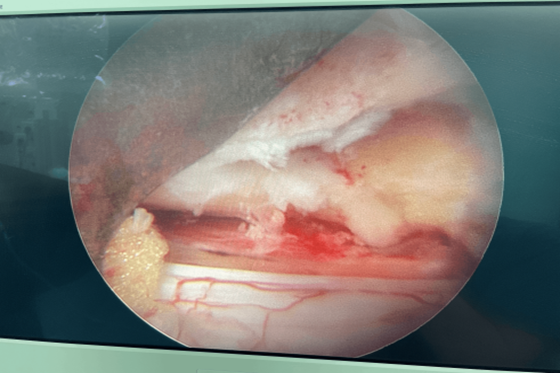

47岁女性患者,因为腰痛和双下肢麻痛长达五年来到湘雅常德医院就诊,其近期活动后双下肢麻痛症状更明显,严重影响生活质量。脊柱外科医师团队对患者进行全方位检查,诊断为“L4-5椎间盘突出合并椎管狭窄”。先对患者展开保守治疗后,效果不明显。经过周密讨论和评估,为患者制定了脊柱微创治疗方案——采用内镜技术下单侧入路“双侧黄韧带切除、髓核摘除、中央椎管减压术。”在麻醉手术部等科室的大力配合下,脊柱外科团队中的陈芳田主任医师、刘磊主治医师、向思宇主治医师合作顺利完成了该手术。患者术后第二天即可下床活动,间歇性跛行症状完全缓解。术后一周即可自由活动,术后一个月复查,患者非常满意微创手术治疗带来的快速康复的效果。

手术中